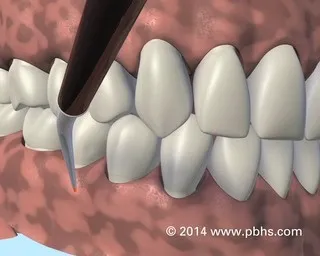

Solution : Scaling

Solution : Scaling & Airflow